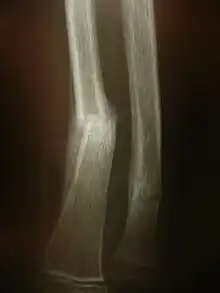

Radiographie montrant une fracture distale de l'avant bras.

Il s'agit des examens radiologiques utilisant la technologie radio la plus « basique ». Un tube à rayon X et une plaque radiologique. Le résultat de cet examen est une radiographie (d'un membre, pulmonaire...).